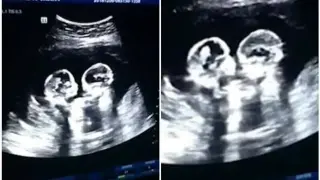

В България няма такъв регистриран случай, откакто се води национална статистика

Нямах представа, че това е възможно. Току-що бях родила близнаци. Отпускът ми по майчинство не трябв...